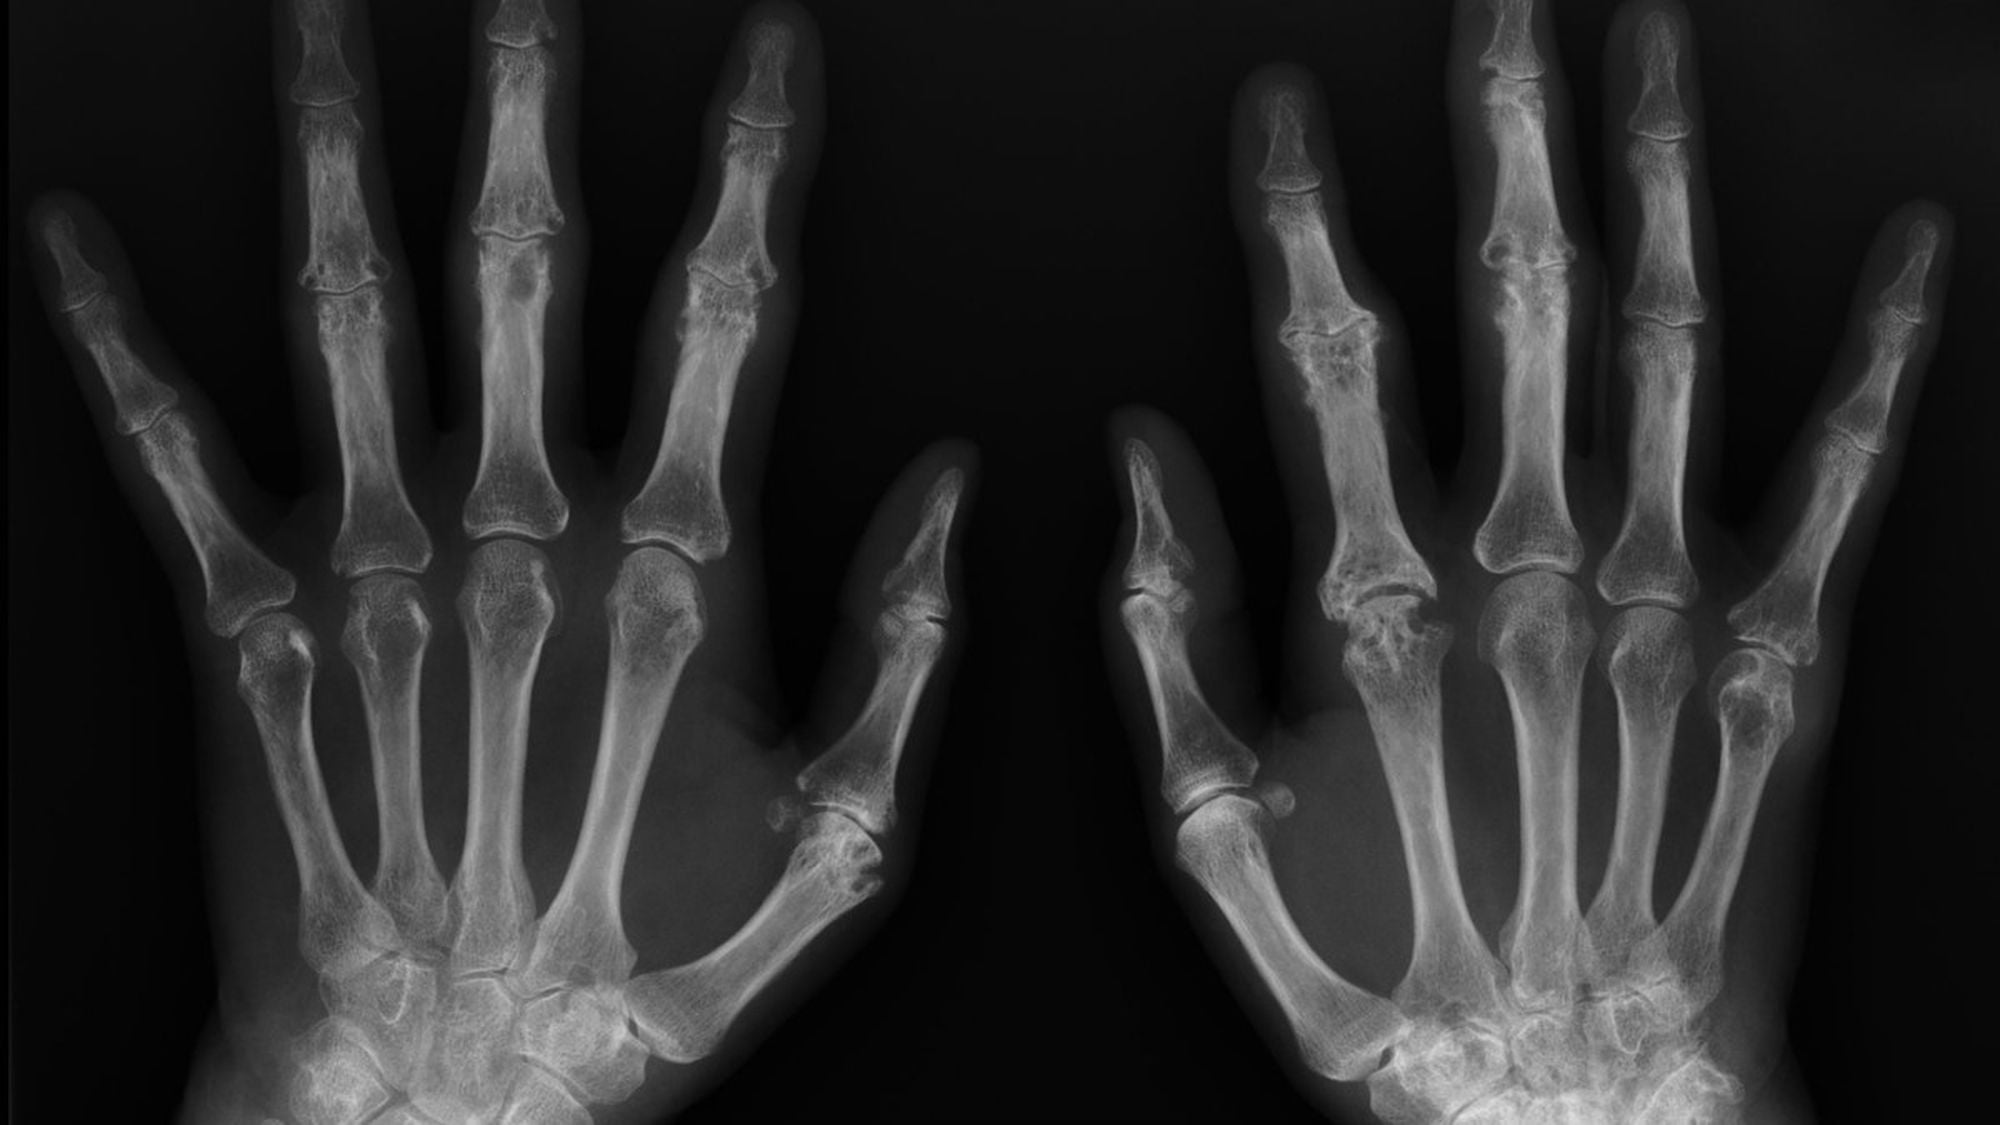

Bebeklikten Yetişkinliğe Ellerimizin X-Işını Görüntüsü ve Kemik Yaşı

Aşağıda gördüğünüz, bir insanın bebekliğinden yetişkinliğine kadar farklı zamanlarda çekilmiş ellerine ait X-Işını Taraması (X-Ray) görüntüleridir.

Bir çocuğun kemiklerinin uçlarında (örneğin parmak ve bilek kemiklerinin uçlarında) "büyüme bölgeleri" olarak da bilinen "büyüme plakaları" bulunur. Bu bölgelerde kemiklerin boylamasına uzamasını sağlayan özelleşmiş hücreler vardır. Bu büyüme plakalarını X-Işını Taraması altında görmek kolaydır, çünkü daha yumuşak yapılıdırlar ve içeriklerinde daha az mineral vardır. Bu da, X-Işını altında diğer dokulara göre daha koyu gözükmelerine neden olur. Görselde, "A" olarak işaretlenmiş fotoğraftaki kemikler arası siyah boşluk bundan kaynaklanır.

Çocuklar büyüdükçe, büyüme plakalarının görünümü de değişir. Giderek daha ince hale gelirler, buna bağlı olarak X-Işını Taraması'nda daha beyaz (yani diğer kemikler gibi) gözükürler ve hatta sonunda tamamen görünmez bile olabilirler. Artık büyük oranda veya tamamen yok olmuş bu plakalara "kapanmış büyüme plakaları" adı verilir. Her bir yaşta farklı gözüktükleri için, sadece kemiklere ve büyüme plakalarına bakarak bir insanın kemik yaşı belirlenebilir. Bunun için doktorlar bir kemik atlasına başvururlar ve söz konusu bireyin plakalarının görünümünün atlastaki hangi kemik yaşına ("iskelet yaşı" olarak da bilinir) denk geldiğini tespit ederler. Böylece bireyin yaşı belirlenebilir.

Bir çocuğun kemik yaşı ile kronolojik yaşı (bizim basitçe "yaş" olarak bildiğimiz versiyonu) arasında eğer ki fark tespit edilirse, ortada bir kemik veya gelişim problemi olduğundan kuşkulanılabilir. Ancak bu mutlaka bir uzman tarafından analiz edilmelidir; zira kimi zaman sağlıklı bireylerde de kronolojik yaş ile kemik yaşı arasında farklılıklar görülebilir.